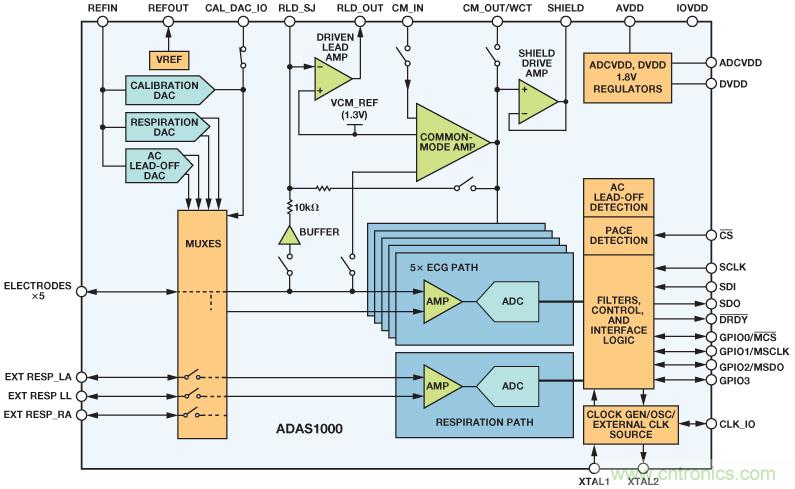

ADAS1000心電圖模擬前端包含起搏偽像檢測算法

ADAS1000(圖8)是一款5通道心電圖(ECG)模擬前端(AFE),旨在幫助解決新一代低功耗、低噪聲、高性能系留式和便攜式ECG系統(tǒng)設(shè)計(jì)人員面對的部分挑戰(zhàn)。ADAS1000專門針對監(jiān)控級和診斷級心電圖測量而設(shè)計(jì),由5個(gè)電極輸入和1個(gè)專用右腿驅(qū)動(dòng)(RLD)輸出參考電極構(gòu)成。

圖8. ADAS1000功能框圖

ADAS1000不但支持基本的心電圖信號監(jiān)控元件,還配有多種功能,比如前面討論過的呼吸測量(胸阻抗測量)、導(dǎo)聯(lián)線/電極連接狀態(tài)、內(nèi)部校準(zhǔn)、起搏偽像檢測功能等。

一個(gè)ADAS1000支持5個(gè)電極輸入,為進(jìn)行傳統(tǒng)的6導(dǎo)聯(lián)心電圖測量提供了方便。通過另外級聯(lián)一個(gè)ADAS1000-2(輔助)器件,系統(tǒng)可以進(jìn)行真正的12導(dǎo)聯(lián)測量;通過級聯(lián)多個(gè)器件(3個(gè)及以上),系統(tǒng)可測量15條及以上的導(dǎo)聯(lián)線。有關(guān)ADAS1000不同變體的詳情,請參閱表1。

ADAS1000的呼吸特性能夠測量患者的胸阻抗變化,從而顯示出呼吸的程度或有無缺失。呼吸功能的核心是在可編程頻率(46 kHz至64 kHz)下集成DAC(數(shù)模數(shù)據(jù)器)呼吸驅(qū)動(dòng),以及有利于簡化這種復(fù)雜測量的專用模數(shù)測量電路。信號經(jīng)過解調(diào),作為幅度和相位信息提供,由此可以確定相應(yīng)的呼吸信息,從而得到具體的線纜參數(shù)。利用內(nèi)部電容,電路能夠檢測最小為200 mΩ的分辨率——使用外部電容時(shí),甚至可以檢測更精確的分辨率——而且開關(guān)方案十分靈活,可對三根導(dǎo)聯(lián)線(I、II、III)之一進(jìn)行測量。

器件的前端包含一種數(shù)字起搏器偽像檢測算法,可以檢測到寬度范圍為100 μs至2 ms、幅度范圍為400 μV至1000 mV的起搏偽像——符合上述AAMI和IEC標(biāo)準(zhǔn)。根據(jù)測試結(jié)果和醫(yī)師意見,這些限制要比醫(yī)用標(biāo)準(zhǔn)寬松許多。

起搏檢測算法在四根可能的導(dǎo)聯(lián)線(I、II、III或aVF)中的三根上運(yùn)行三個(gè)數(shù)字算法實(shí)例。在高頻心電圖數(shù)據(jù)上運(yùn)行,與內(nèi)部抽取和濾波并行運(yùn)行。該算法設(shè)計(jì)用于檢測并測量寬度范圍為100 μs至2 ms、幅度范圍為400 μV至1000 mV的起搏偽像,返回一個(gè)標(biāo)志,用以表示是在一根還是多根導(dǎo)聯(lián)線上檢測到起搏信號,同時(shí)返回檢測到的信號的高度和寬度。對于希望運(yùn)行自己的數(shù)字起搏算法的用戶,ADAS1000提供了一個(gè)高速起搏接口,可以快速的數(shù)據(jù)速率(128 kHz)提供心電圖數(shù)據(jù),與此同時(shí),標(biāo)準(zhǔn)接口上經(jīng)過濾波和抽取的心電數(shù)據(jù)保持不變。

ADAS1000 ECG IC在其算法中內(nèi)置一個(gè)分鐘通氣量濾波器。分鐘通氣量脈沖(從雙極性導(dǎo)聯(lián)線的圓環(huán)傳導(dǎo)至起搏器外殼)將檢測呼吸速率,從而控制起搏速率。其寬度總是小于100 μs,變化范圍約為15 μs至100 μs。

這種起搏偽像系統(tǒng)是由一個(gè)工程師和起搏專家團(tuán)隊(duì)與起搏行業(yè)共同研發(fā)的。這種合作帶來了一種同步三矢量起搏偽像檢測系統(tǒng),該系統(tǒng)可以檢測起搏偽像,盡管電氣噪聲顯著大于偽像。三個(gè)起搏算法實(shí)例中的每個(gè)實(shí)例都可以編程以檢測不同導(dǎo)聯(lián)線(I、II、II或aVF)上的起搏信號。該系統(tǒng)的閾值水平可編程,因而可以針對實(shí)際的脈沖寬度和高度檢測范圍進(jìn)行定制,同時(shí)還配置內(nèi)部數(shù)字濾波器,以便抑制心跳、噪聲和分鐘通氣量脈沖。當(dāng)證實(shí)起搏信號的單個(gè)實(shí)例中存在起搏信號時(shí),器件會(huì)輸出一個(gè)標(biāo)志,因而,用戶可以在心電圖上標(biāo)記或識別出起搏信號。

起搏偽像算法的采樣速率選擇非常重要,因?yàn)椴荒芘cMedtronic、St. Jude和Boston Scientific針對H場遙測載波器采用的頻率完全相同。三家公司都采用不同的頻率,而且每家公司都有多種不同的遙測系統(tǒng)。ADI公司相信,ADAS1000所用采樣頻率與這三家起搏器廠家的主要遙測系統(tǒng)都不相同。

如前所述,ADAS1000同時(shí)包括呼吸測量和交流導(dǎo)聯(lián)脫落模式。這些特性不但可以把不同頻率的交流信號注入患者電極,而且不會(huì)干擾起搏偽像的采集。電灼器信號雖然可以在ADAS1000心電圖輸入之前進(jìn)行濾波處理,但起搏偽像檢測算法的性能卻可能因?yàn)V波而下降,因此,在這種設(shè)計(jì)中,務(wù)必十分小心。